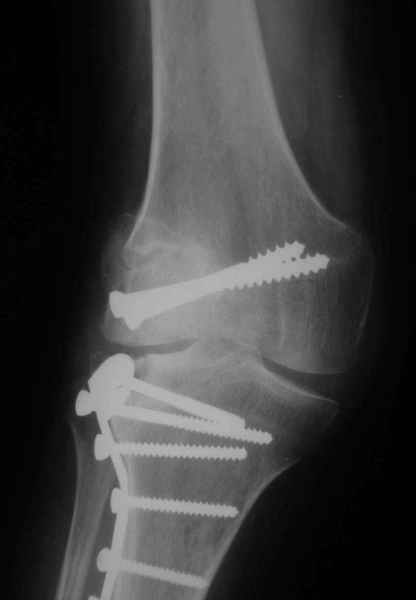

На прием обратилась больная 38 лет. Травма 17.01.2005. 23.01.2005 - операция в одном из стационаров области - остеосинтез мыщелка бедра винтами, Остосинтез мыщелка большеберцовой кости L-образной пластиной.

Остальные снимки Ноябрь 2005

Иммобилизация лонгетной гипсовой повязкой 2 мес. После прекращения иммобилизации, пр начале ЛФК отмечена нарастающая вальгусная деформация конечности. Рентгенограммы в приложении. Хотелось бы узнать Ваши предложения по тактике лечения